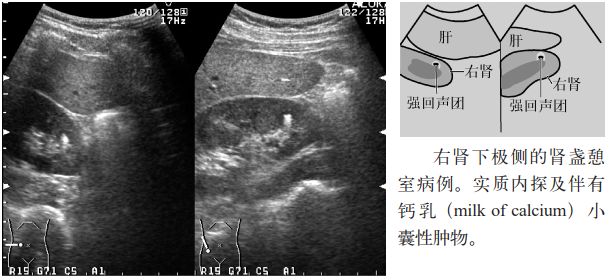

图4 珊瑚状结石

3.肾盏憩室或肾盏积水的内部常见沉积物样高回声(钙乳)或结石。